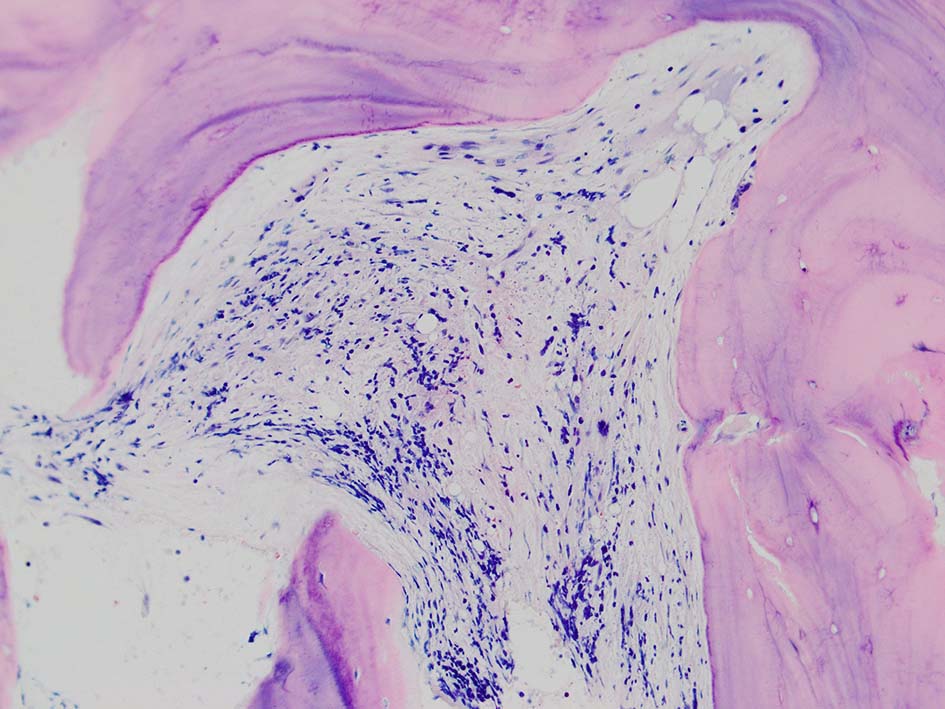

骨髄壊死(BMN)は,造血性骨髄(BM)の髄質間質と骨髄組織の広範囲な壊死を特徴とするユニークな臨床病理学的病態であり、無定形の好酸球性背景、由来不明瞭な壊死細胞、皮質骨の温存が認められる.*1

骨髄生検組織では骨梁間に壊死に陥った細胞の凝固壊死像が確認できる. 本例では脂肪細胞は消失せず形態が残っている.壊死のあとには, 髄腔に線維化をきたす. 上図には線維化を示し, 右端の図では壊死巣と線維化の境界が観察される.

本例ではviableな腫瘍細胞がハーバース管と考えられる管内に認められた.(髄腔とハーバース管腔は解剖学的に同じ場所といえるのか?)

ハーバース管は緻密骨内の骨構造であり, 管内には動静脈, 脈管周囲リンパ管, 神経線維が入る. 解剖学的に海綿骨骨髄腔とは異なる空間構造と考えられる.--viableな腫瘍細胞の存在はリンパ管、血管内への腫瘍浸潤と考えられる.